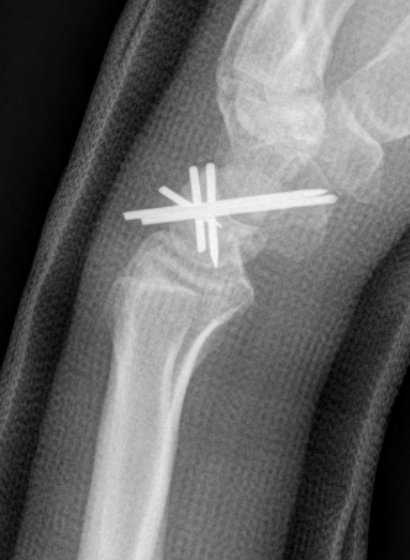

Perilunate fracture-dislocations / Trans-scaphoid perilunate

Dorsal approach

- 3/4 extensor compartment

- mobilise EPL laterally

- capsulotomy: T shaped or Berger (open dorsal between DRC and DIC ligaments)

- ORIF scaphoid fracture with headless compression screws

- assess stability of scapho-capitate and scapholunte joint (often ligaments intact and stable)

- K wires lunate-triquetral +/-

- +/- repair LT ligament

- +/- ORIF capitate

+/- volar approach

- reduce lunate

- carpal tunnel decompression

- repair rent in capsule